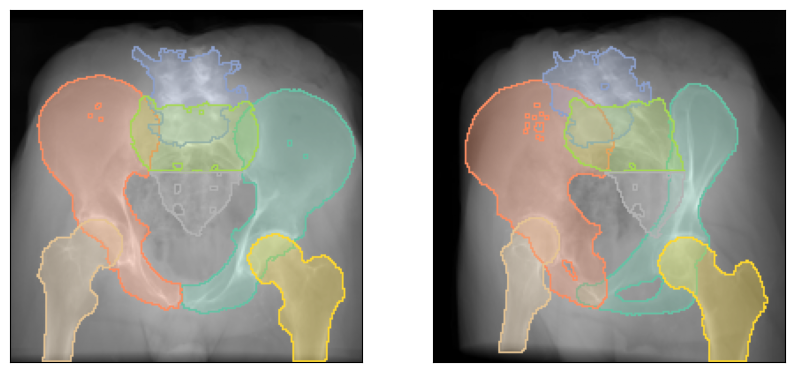

Class interface¶

The traditional class interface from DiffDRR is also available if you wish to have fixed intrinsics.

However, note that the new class interface also let's you freely change the user at runtime.

# Render with fixed intrinsics

img = drr(subject, rt_inv)

plot_drr(img, ticks=False)

plt.show()